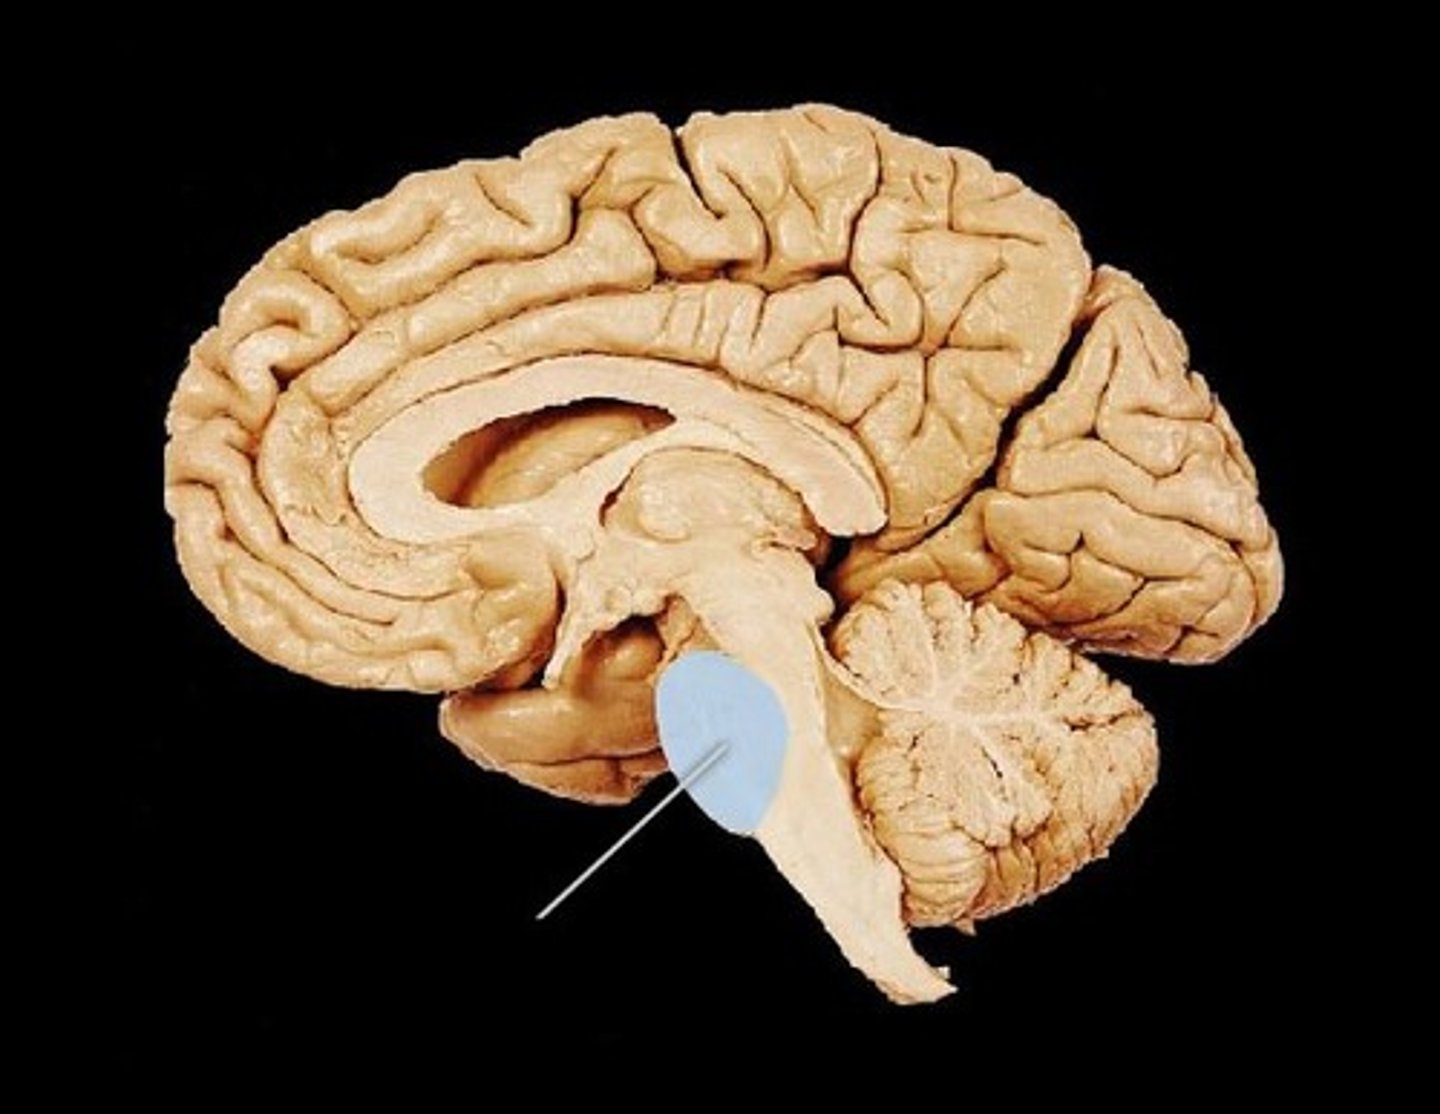

has pons, cerebrellum, and upper part of the 4th ventricle

has medulla oblongata and lower 4th ventricle

tentorium cerebelli

2nd largest, crescent-shaped, separates cerebrum (occipital lobes) from cerebellum (arrow #5)

pons

center structure of the brain stem, located between the midbrain and the medulla oblongata

midbrain

or mesencephalon extends from pons to diencephalon. the pons is the center structure of the brain stem, located between the midbrain and the medulla oblongata